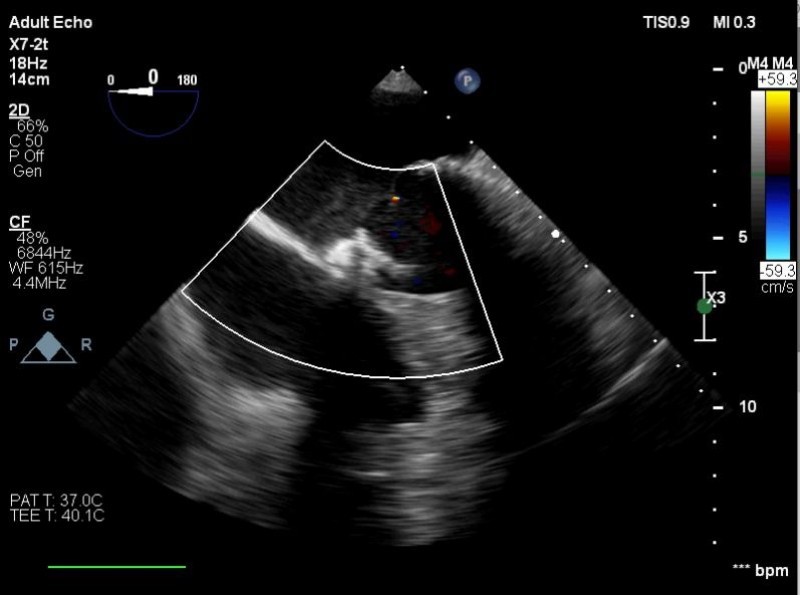

Yapılan işlemi gerçekleştiren ekipte yer alan Prof. Dr. Halil Kısacık, Doç. Dr. Eyüp Avcı, Doç. Dr. Tarık Yıldırım ve Doç. Dr. Özgen Şafak konu hakkında açıklamalarda bulundu. Daha önce kalp kapakçığı değişim ameliyatı olan hastada takılan kapağın kenarından ayrılmasıyla kan kaçağı (paravalvuler leak) meydana geldiğini belirten öğretim üyeleri, Kardiyoloji Anabilim Dalına başvuran hastaya, Türkiye’de sayılı kalp merkezinde yapılan ve önemli düzeyde cerrahi deneyim gerektiren paravalvüler kaçak kapatılması işlemi uygulandığını dile getirdi. İşlemin sadece girişimsel kardiyologlar tarafından yapıldığının altını çizen öğretim üyeleri, işlem sırasında hastanın kalbi durdurulmadan ve göğüs kafesi kesilmeden, kasığından girilerek yapay kalp kapağındaki kaçağın ameliyatsız kapatıldığını söyledi.